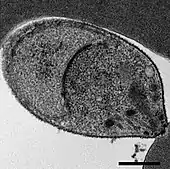

| Giemsa-stained smears of Plasmodium knowlesi infecting human red blood cells | |

Malaria is traditionally diagnosed by examining Giemsa-stained blood films under a microscope; however, differentiating P. knowlesi from other Plasmodium species in this way is challenging due to their similar appearance.[11] P. knowlesi ring-stage parasites stained with Giemsa resemble P. falciparum ring stages, appearing as a circle with one or two dark dots of chromatin.[17] Older trophozoites appear more dispersed, forming a rectangular-shape spread across the host cell called a "band-form" that resembles the similar stage in P. malariae.[17] During this stage, dots sometimes appear across the host red blood cell, called "Sinton and Mulligans' stippling".[17] Schizonts appear, similarly to other Plasmodium species, as clusters of purple merozoites surrounding a central dark-colored pigment.[17]